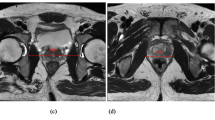

MRI was performed using the 1.5-T or 3.0-T MR system (Signa Premier or Signa HDx; GE Medical Systems, Waukesha, WI, USA or Ingenia, Philips Healthcare, Best, The Netherlands) with a multichannel anterior array coil combined with a multichannel posterior table coil. MRI was performed preoperatively and within 1 week of postoperative indwelling catheter removal. MRI was performed 30–60 min after urination. The estimated bladder capacity in each patient was 30–100 mL based on the MRI results. After multiplanar T2-weighted axial section imaging, an adequate sagittal section was created to capture the prostatic urethra. Sagittal dynamic MRI was performed at rest and during the abdominal pressure phase using a fast spin-echo sequence with the following parameters: repetition time/echo time, 1500–3716 ms/85–104 ms; flap angle, 90°; slice thickness, 6 mm; field of view, 300 mm; and imaging matrix, 224–352 × 156–224. Figure 1 illustrates the following measurements: distance from the distal end of the membranous urethra to the pelvic outlet (DMU-PO)11,12, distance from the bladder attachment to the pubic symphysis (BA-PS), the MUL, prostate length (PL), distance from the pubic symphysis to the prostate apex length (PAL)13, and the length from the bladder neck to the pubic symphysis (BN-PS)8. Figure 2 shows the dynamic mid-sagittal MRI after C-RARP and RS-RARP, performed preoperatively and postoperatively, at rest and with abdominal pressure. Figure 3 illustrates the measurement of the external urethral sphincter thickness, defined as the distance from the lowest point of the pubic bone to the anterior edge of the rectal wall, at rest and with abdominal pressure using MRI after C-RARP and RS-RARP. The compression distance was defined as the thickness of the external urethral sphincter at rest minus the thickness during abdominal pressure.

Dynamic mid-sagittal magnetic resonance imaging (MRI) after conventional robot-assisted radical prostatectomy (RARP): at rest (A) and with abdominal pressure (B). Dynamic mid-sagittal MRI after Retzius-sparing RARP: at rest (C) and with abdominal pressure (D). The thickness of the external urethral sphincter (two-headed red arrow) defined as the distance from the lowest point of the pubic bone to the anterior edge of the rectal wall (blue dashed line) was measured at rest and with abdominal pressure (orange arrow). The external urethral sphincter is indicated by the box surrounded by the red dashed line.

In addition to static MRI, dynamic MRI was performed postoperatively in 45 C-RARP patients and 44 RS-RARP patients. Postoperatively, the compression distances were significantly longer in patients who underwent RS-RARP than in those who underwent C-RARP (Fig. 5).